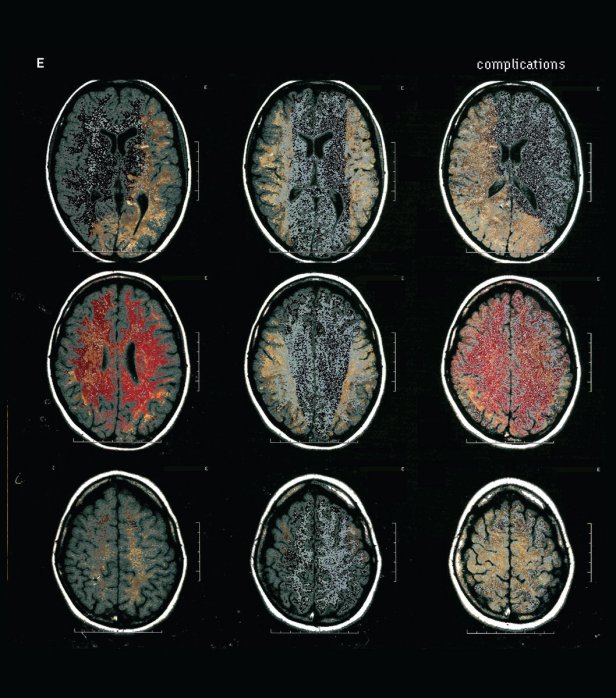

12. E – Complications

Een van de mooiste gitaarplaten van het jaar komt niet van een jong bandje, maar van drie ervaren rotten die zich E noemen en opereren vanuit Boston. Thalia Zedek (Come, Live Skull, Uzi, Thalia Zedek Band), Gavin McCarthy Karate, Thalia Zedek Band) en Jason Sidney Sanford (Neptune) bewijzen bijna achteloos dat zij er toe doen. De gitaren zijn constant in de weer en blijven niet hangen in obligate riffs of lijnen. De wat droge sound, zonder franje, past bij deze band. De muziek klinkt vitaal, stekelig en gedreven. Natuurlijk zijn er raakvlakken met het verleden, maar E hoeft anno 2020 niet te vrezen als anachronisme te worden weggezet.